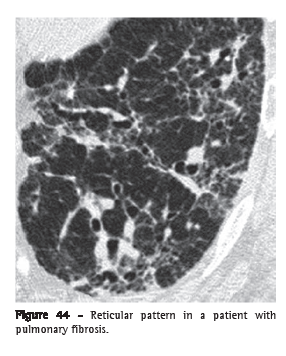

Reticular pattern (padrão reticular)The reticular pattern is an alteration that is usually associated with interstitial diseases and is radiographically characterized by innumerable linear opacities that produce a net-like appearance.(1) On HRCT scans, it is possible to single out the components responsible for this radiographic pattern, usually related to the presence of interlobular and septal lines (Figure 44) or to the presence of cysts with walls giving the radiographic appearance of lines, such as in pulmonary cystic diseases, in bullae-related emphysema and even in honeycombing cysts.(1,3,7)